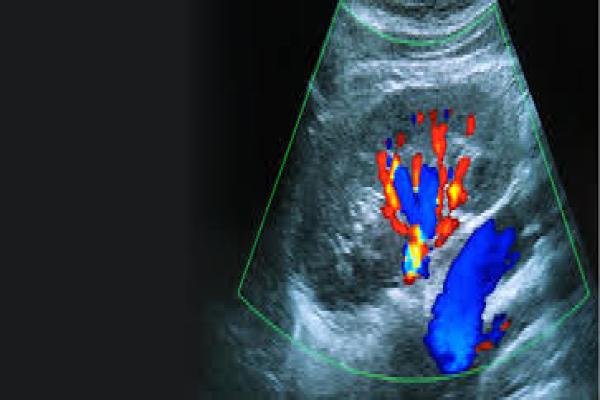

Color Doppler Scan

Used to evaluate blood flow between mother, placenta, and baby, especially in high-risk pregnancies.